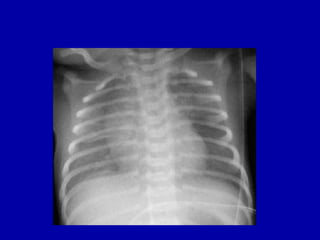

X-ray – Congenital pneumonia

Congenital pneumonia

Predisposing factors

PROM >24 hours, foul smelling liquor,

Peripartal fever, unclean or multiple per

vaginal

Treatment

Thermoneutral environment, NPO, IV

fluids, Oxygen, antibiotics-